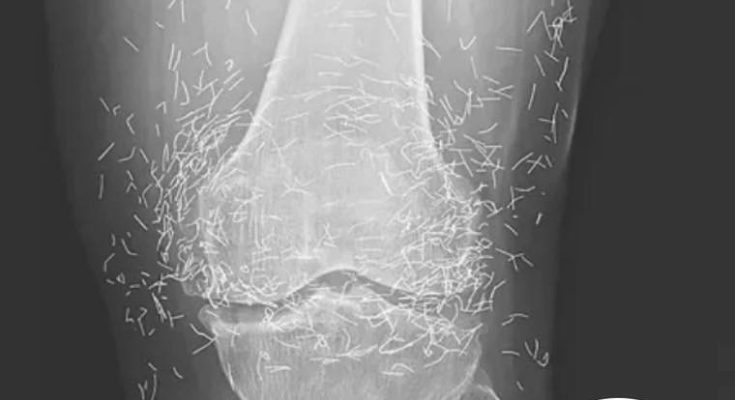

A routine X-ray revealed an unexpected surprise when doctors examined the knees of a 65-year-old woman suffering from severe joint pain. What they found was nothing short of astonishing — hundreds of tiny gold needles embedded deep in her tissue.

There are other complications as well. Needles lodged in tissue can interfere with medical imaging. “They can obscure parts of the anatomy on an X-ray,” Guermazi noted. Even more alarming, patients with metal fragments in their bodies should never undergo an MRI, as the magnetic force could cause the needles to move — potentially puncturing blood vessels and causing life-threatening damage.

A X-ray of the patient’s knee showing acupuncture needles embedded in the tissue, Photo Credit: Reddit

As for the South Korean woman, her case was recently documented in the New England Journal of Medicine. While the needles may have been intended to help, her X-rays tell a cautionary tale about the potential risks of extreme alternative therapies.